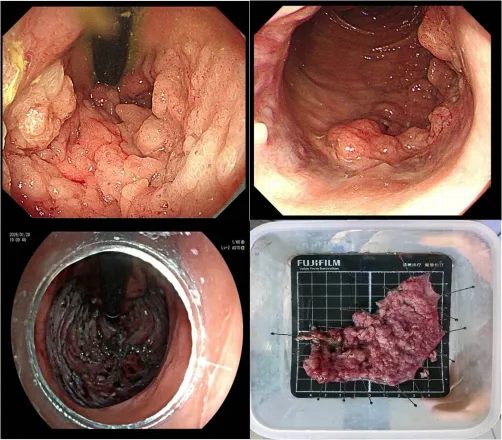

手术在麻醉团队的护航下展开。梅璐副主任医师操作高清电子肠镜,清晰观察肿瘤范围与边界,精细标记后,使用高频黏膜切开刀逐步切开并剥离病灶。肿瘤体积大、血供丰富,且直肠黏膜薄、操作空间狭小,对术者的经验与技巧提出极高要求。团队凭借精湛技术,在4小时内将约11cm×11cm的肿瘤完整剥离,术中出血仅20ml,未损伤肛门括约肌及周围重要结构,无并发症发生。术后病理证实切缘阴性,达到临床治愈。